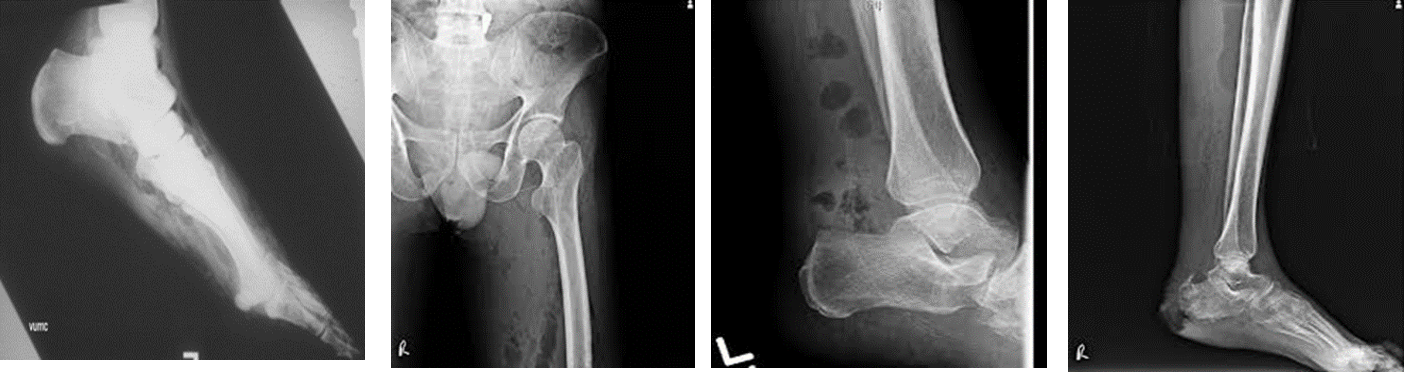

• X-ray: ( appearance of gas under skin and in muscles.)